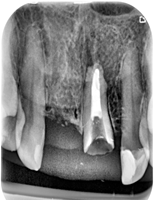

Pacjentka zgłosiła się z bólem. Kilka miesięcy wcześniej leczona kanałowo lewa dolna szóstka. Ząb wrażliwy na nagryzanie. Podjęto decyzję o ponownym przeleczeniu kanałów korzeniowych. Zamknięto perforację przy wejściu do dalszego kanału, usunięto złamaną igłę lentulo z dalszego kanału, udrożniono mezjalne kanały, aż do perforacji korzenia w policzkowym bliższym kanale. Wypełniono dalszy kanał gutaperką, bliższe kanały wypełniono MTA. Ząb do obserwacji, najprawdopodobniej będzie wykonana resekcja wierzchołków bliższego korzenia, na poziomie perforacji.

Reendo 46.